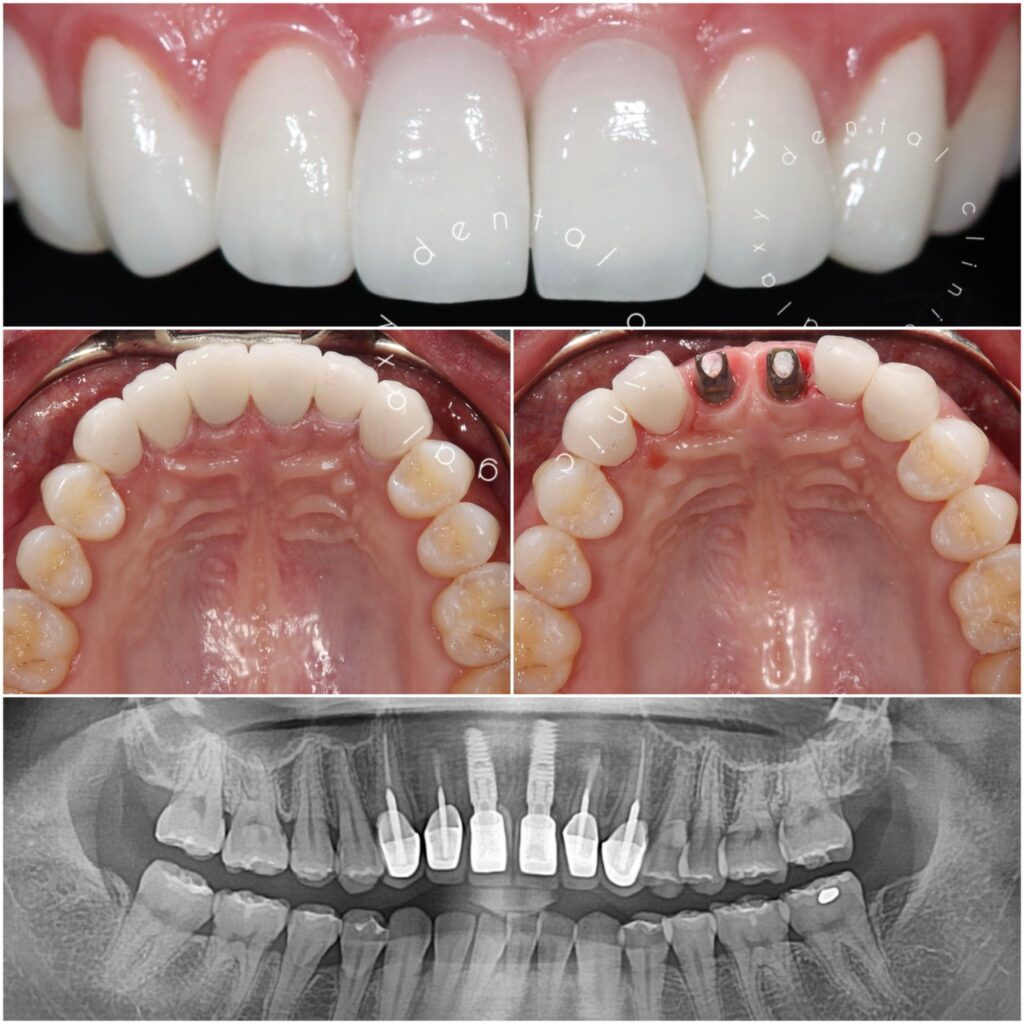

Tôi sống ở Mỹ. Tôi từng sống rất không tự tin vì răng của mình. Tình cờ lên mạng thấy Galaxy Dental Clinic có tư vấn miễn phí, tôi đã gọi điện và được yêu cầu chụp hình răng gửi qua email. Sau đó, tôi nhận được hồi âm là cách giải quyết rất cụ thể và chi tiết. Tôi đặt lịch hẹn và bay về Việt Nam, tìm tới Galaxy Dental Clinic để làm răng. Tôi rất cám ơn và khâm phục trình độ chuyên môn của bác sĩ tại đây. Và thời gian hoàn thiện thật nhanh chóng

Tại Galaxy Dental Clinic, tôi đã được bác sĩ tư vấn về phương pháp điều trị dán sứ veneer. Tôi rất cảm ơn Galaxy Dental Clinic, đặc biệt là bác sĩ Mừng đã rất tận tâm và nhiệt tình để tôi có được một hàm răng đẹp tự nhiên, ưng ý nhất. Sau 1 năm điều trị, tôi rất tự tin với hàm răng mới và ăn nhai rất thoải mái